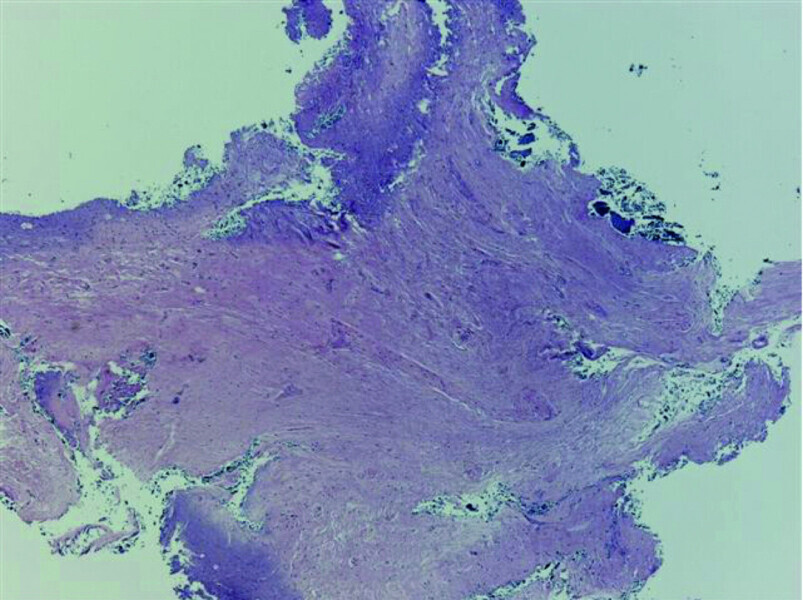

Fig. 20: Tissue removed from the endodontic space three months after transplantation (H&E stain; 2× magnification).

Fig. 21: Tissue removed from the endodontic space three months after transplantation (H&E stain; 4× magnification).